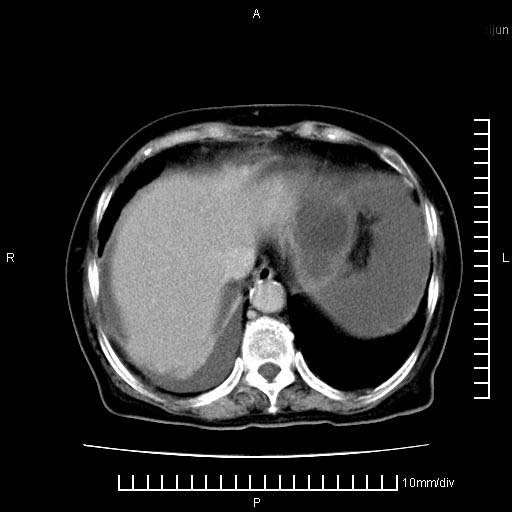

标题: CT28280:腹部增强:女性,80岁

上腹疼痛月余,外院核磁诊断胰腺癌。现临床示右下腹可明显触及包块,可片子上怎么没有看到?

1。胰腺ca伴腹膜腔转移

2。肝左叶低密度灶,考虑转移可能

支持胰腺癌肝内转移,腹水改变。

1、考虑胰腺癌伴腹膜腔转移,胸腹水。

2、肝脏转移可能。

考虑胰腺ca伴腹膜腔转移、肝左叶转移、右肾积水。右胸腔积液。